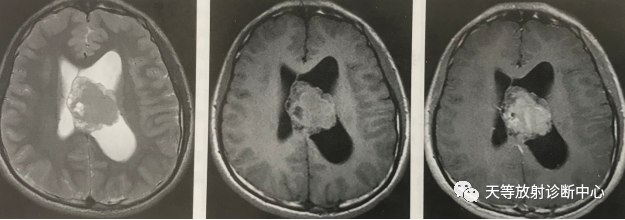

病例1:中枢神经细胞瘤:

T2WI及T1WI左侧侧脑室内不规整肿块影,分叶状,信号不均,以等高信号混杂,透明隔右移位,增强扫描肿块明显强化。(《磁共振成像临床应用入门》主编:靳二虎、蒋涛、张辉)